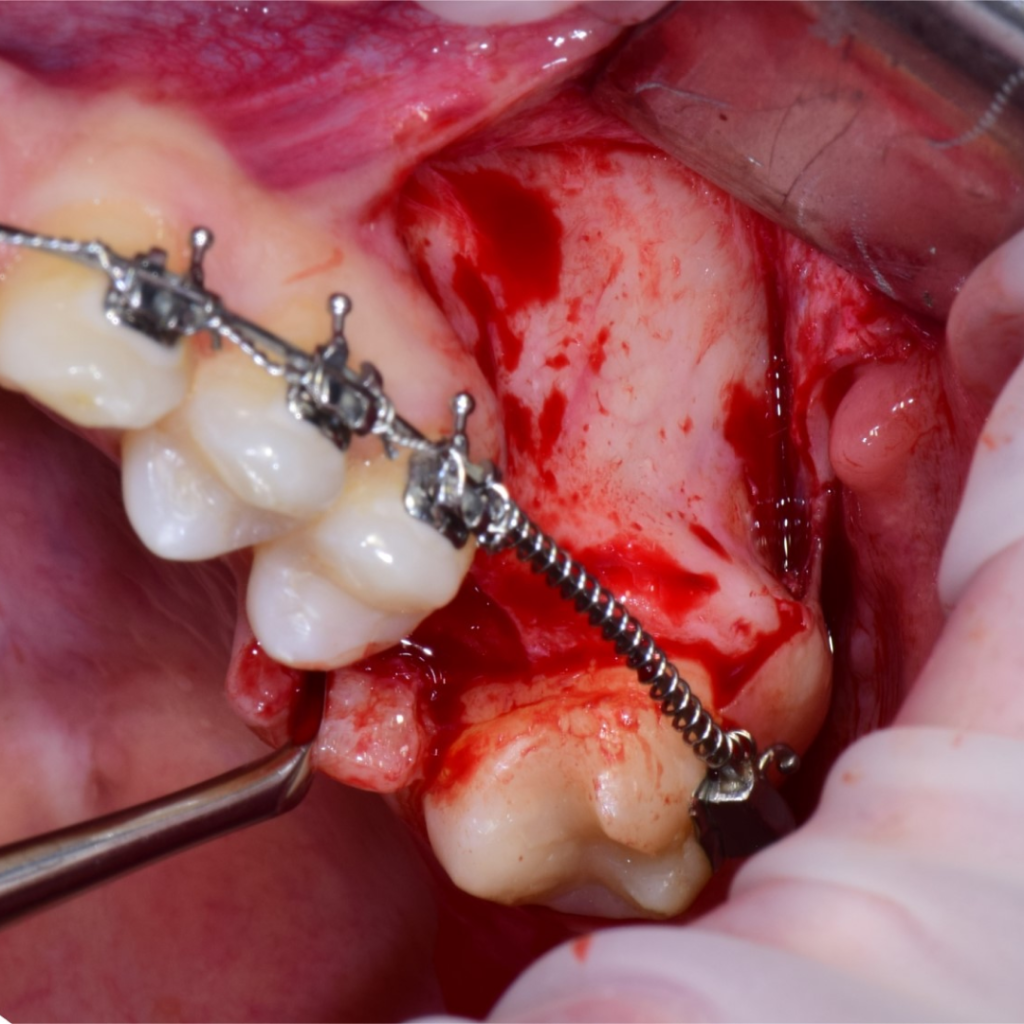

По результатам диагностики принято решение провести синус-лифтинг с помощью боров SinPro. В ходе вмешательства установлены имплантаты AnyRidge и AnyOne с первичной стабилизацией 40 Ncm.